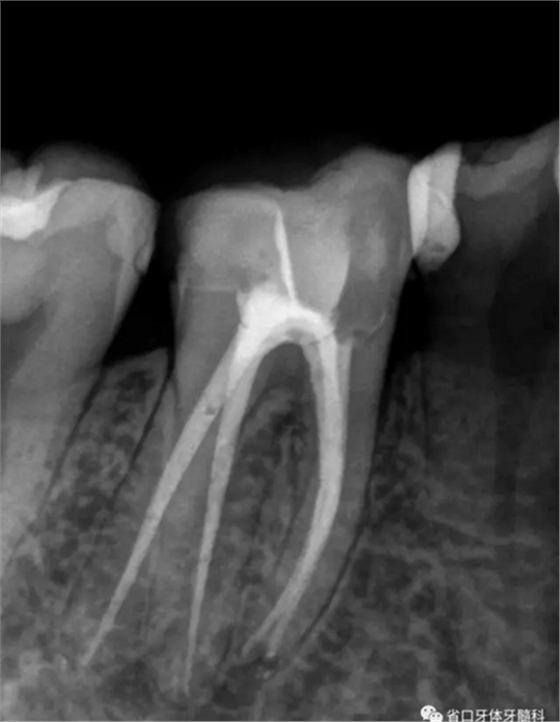

圖1 術前X線片:46/近中根面繼發(fā)齲,根尖周低密度影,遠中舌側根管影像模糊;根分叉低密度影,近中牙槽骨見少許角形吸收。

圖2 術后根充片

術后隨訪x線片,遠頰、遠舌根尖低密度影消失,近頰根尖低密度影局限(提示近頰根尖瘢痕愈合),嵌體不阻射x線。